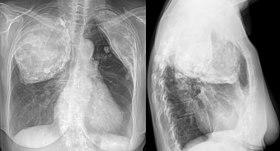

Oleothorax bei Tuberkulose 80jw - Roe ap und seitlich - 001.jpg

X-ray in an elderly woman after Pneumonolysis